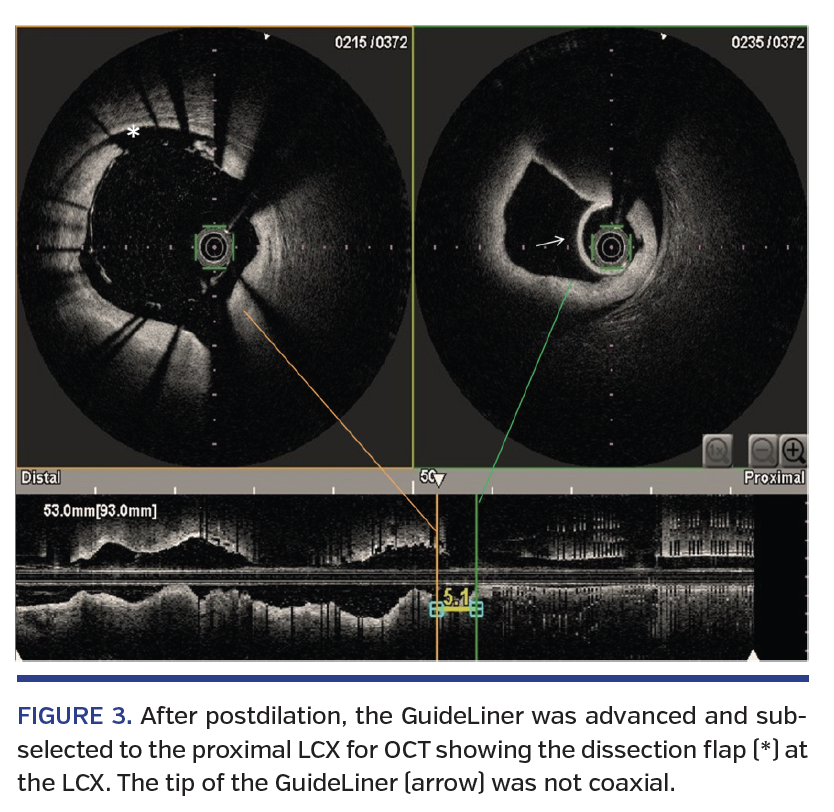

A 54-year-old man presented with non-ST elevation myocardial infarction. Coronary angiogram showed two-vessel disease with severe stenosis in the mid left anterior descending (LAD) artery and proximal and distal left circumflex (LCX) artery (Figure 1). Percutaneous coronary intervention (PCI) to the LCX was performed under optical coherence tomography (OCT) guidance. A 3 x 40 mm drug-eluting stent (DES) was implanted in the LCX, but landed more proximally than intended due to breathing motion. As a result, there was gross malapposition of the proximal stent as shown by OCT (Figure 2). To facilitate delivery of a 4 mm non-compliant balloon across the malapposed stent, a 6 Fr GuideLiner “child” support catheter (Vascular Solutions) was inserted into the existing “mother” 6 Fr guiding catheter to provide extra coaxial back-up support. OCT imaging of the LCX after stent postdilation was suboptimal due to preferential contrast flow into the large LAD. Therefore, the soft GuideLiner tip was advanced into the proximal LCX to provide selective contrast injection to enhance OCT imaging. Our practice routinely uses very-short hand injection of 10-12 mL contrast for OCT image acquisition.

Angiography after OCT acquisition showed hydraulic spiral dissection from the proximal LCX extending retrograde into the proximal LAD and distal left main (LM) stem (Figures 3 and 4; Video 2). A 4.0 mm semicompliant (SC) balloon was immediately inflated at the LCX dissection site for 1 minute. Subsequent angiogram with balloon occlusion of the LCX showed patent LAD with no contrast staining (Figure 5). A 4 x 24 mm DES was implanted from the LM into the LCX, overlapping the initial LCX stent. The final angiogram was satisfactory and the patient remained stable throughout the procedure.

Mother-and-child catheter pairing the GuideLiner support catheter delivered through a standard guiding catheter permits deep intubation of the target vessel to provide coaxial back-up support to facilitate stent delivery across heavily calcified lesions in tortuous vessels and selective contrast injection. In this case, the soft tip of the GuideLiner was not coaxial to the tortuous LCX and likely abutted the vessel wall or plaque despite no warning of pressure damping before contrast injection during OCT acquisition. Focal hydraulic pressure generated by short and forceful hand contrast injection could easily create a crack at a vulnerable plaque and track into the injury point, resulting in coronary dissection. Therefore, positioning of the GuideLiner for OCT acquisition in tortuous vessels requires special attention to avoid iatrogenic dissection.